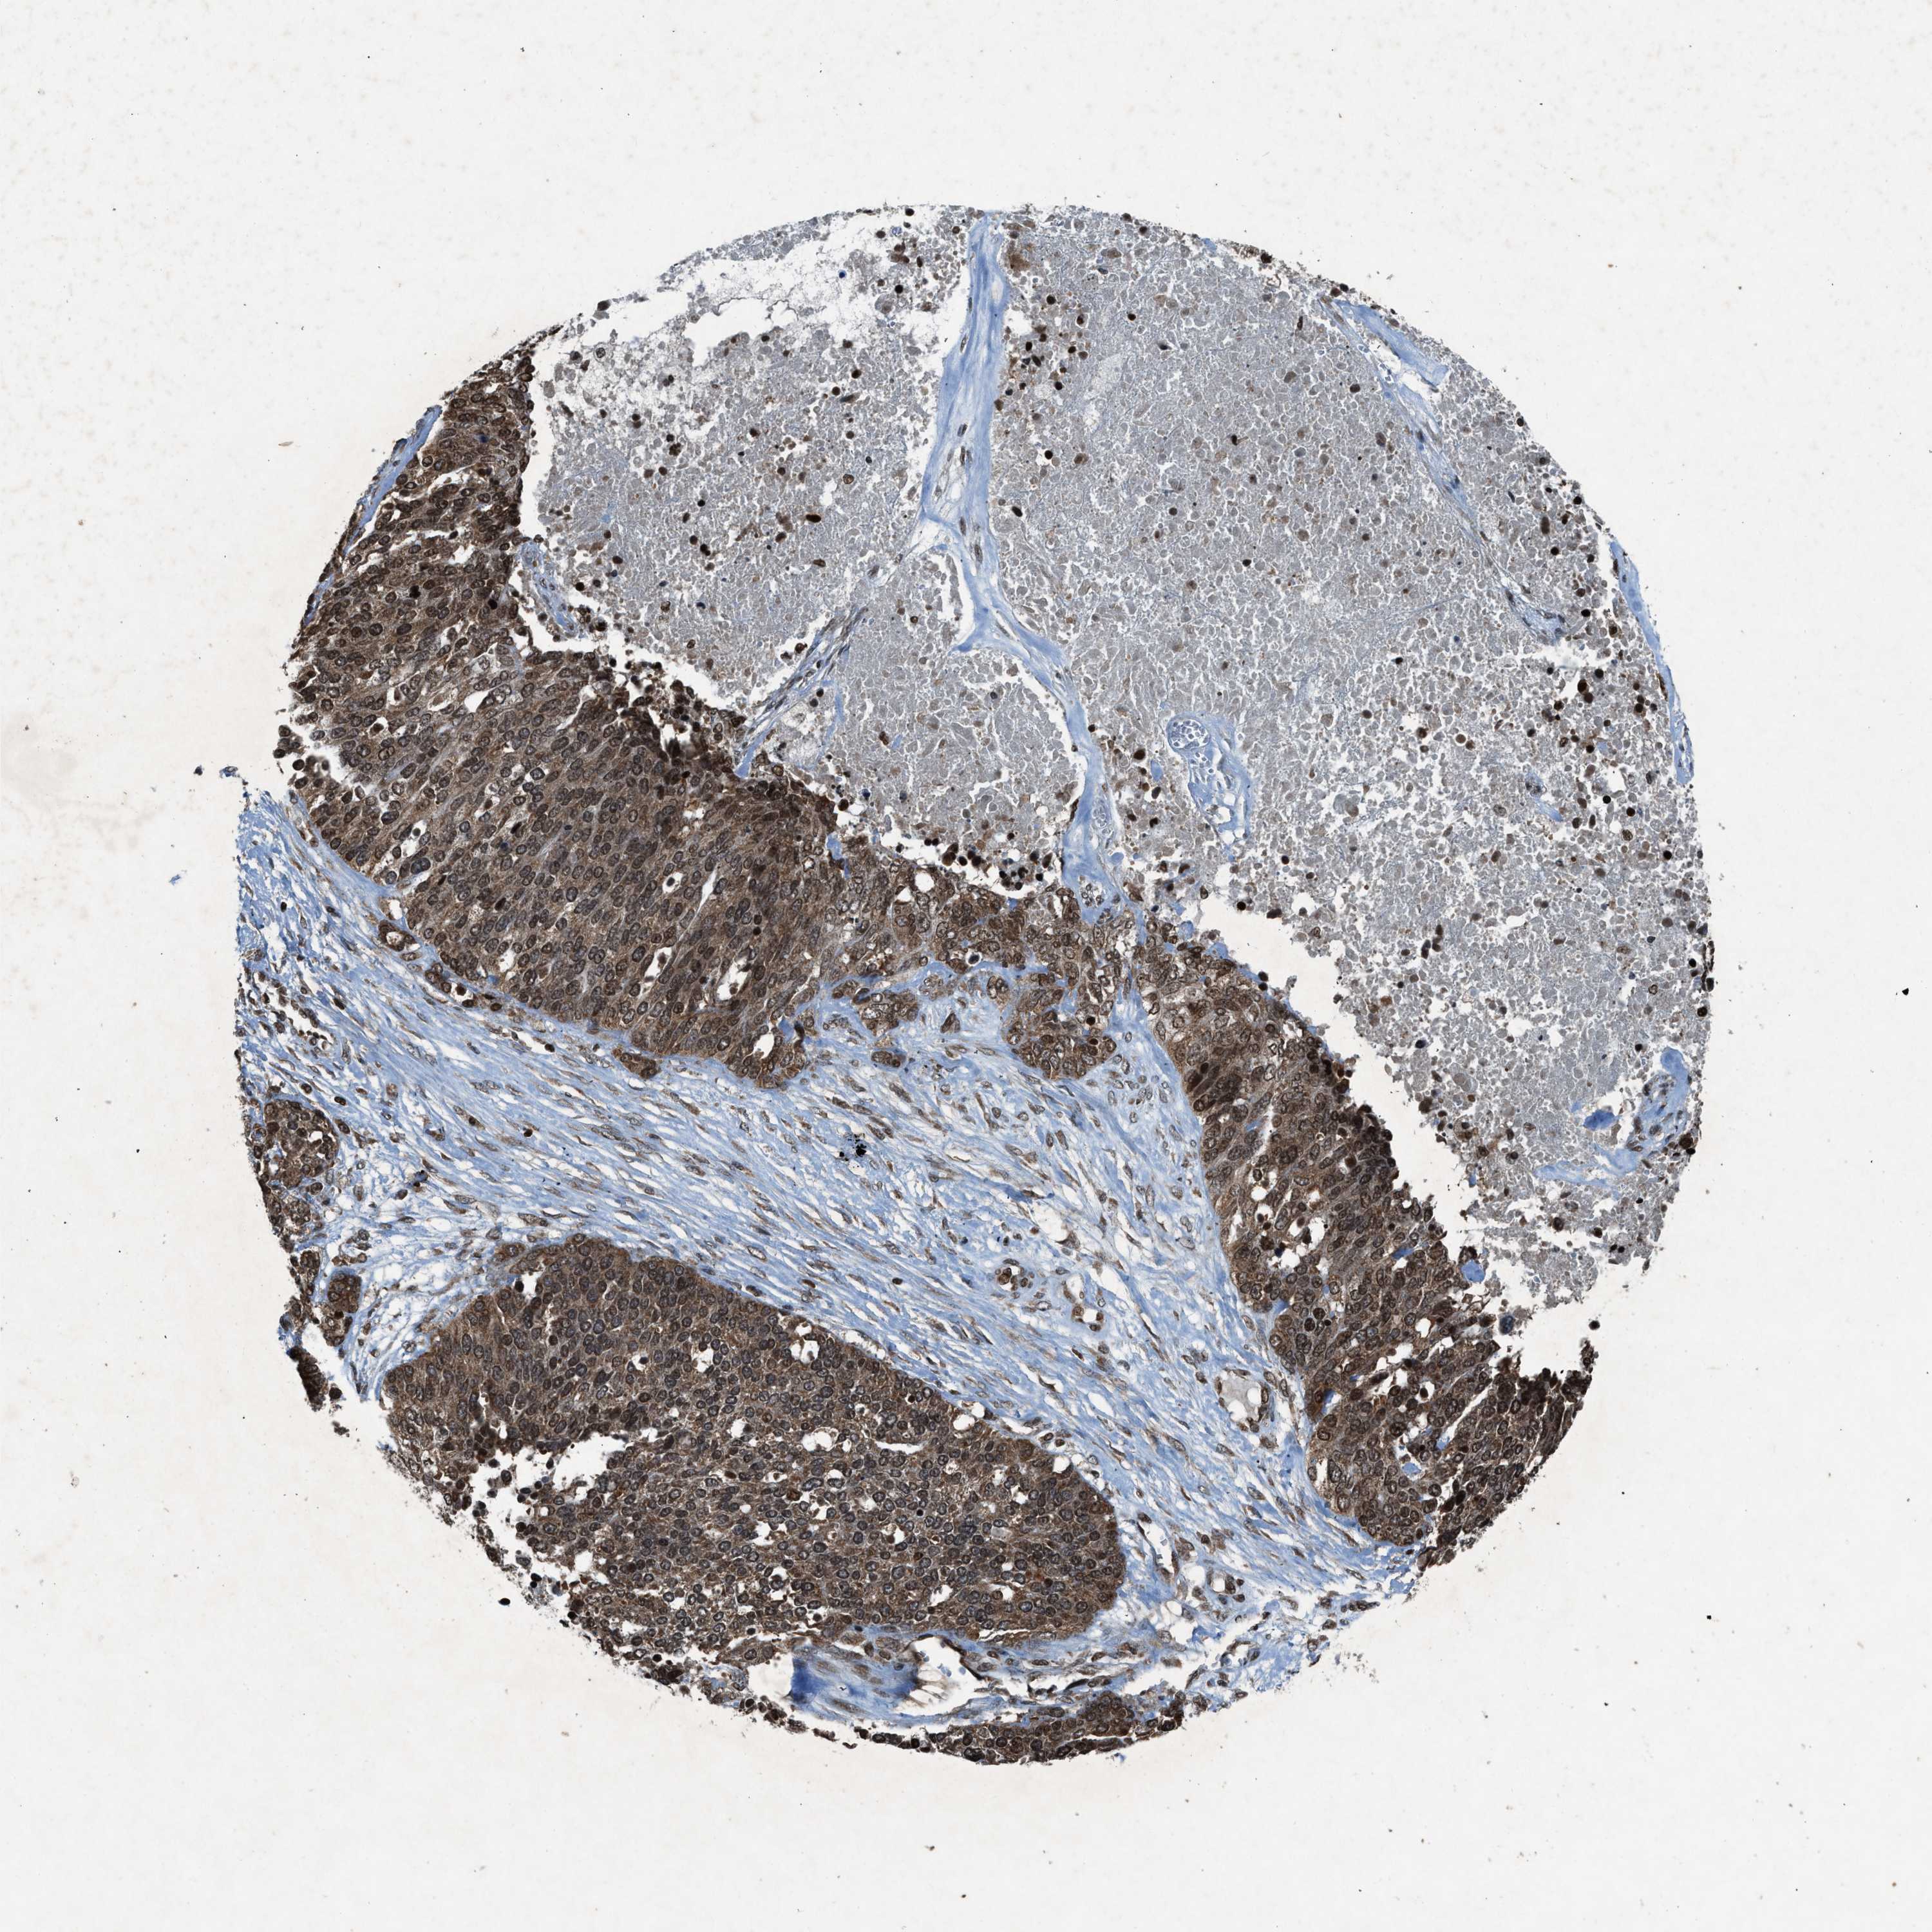

OVARIAN CANCER - Protein expressioni

A mouse-over function shows sample information and annotation data. Click on an image to view it in a full screen mode. Samples can be filtered based on level of antibody staining by selecting one or several of the following categories: high, medium, low and not detected. The assay and annotation is described here.

Note that samples used for immunohistochemistry by the Human Protein Atlas do not correspond to samples in the TCGA dataset.

Antibody stainingi

Antibody staining in the annotated cell types in the current human tissue is reported as not detected, low, medium, or high, based on conventional immunohistochemistry profiling in selected tissues. This score is based on the combination of the staining intensity and fraction of stained cells.

Each image is clickable and will lead to virtual microscopy that enables deeper exploration of all samples and also displays staining intensity scores, fraction scores and subcellular localization as well as patient and tissue information for each sample.

Antibody HPA061593

Antibody CAB016327

Staining

High

Medium

Low

Not detected

Intensity

Strong

Moderate

Weak

Negative

Quantity

>75%

75%-25%

<25%

None

Location

Nuclear

Cytoplasmic/membranous

Cytoplasmic/membranous,nuclear

Cystadenocarcinoma, serous, NOS

Cystadenocarcinoma, mucinous, NOS

Carcinoma, endometroid

Carcinoma, NOS